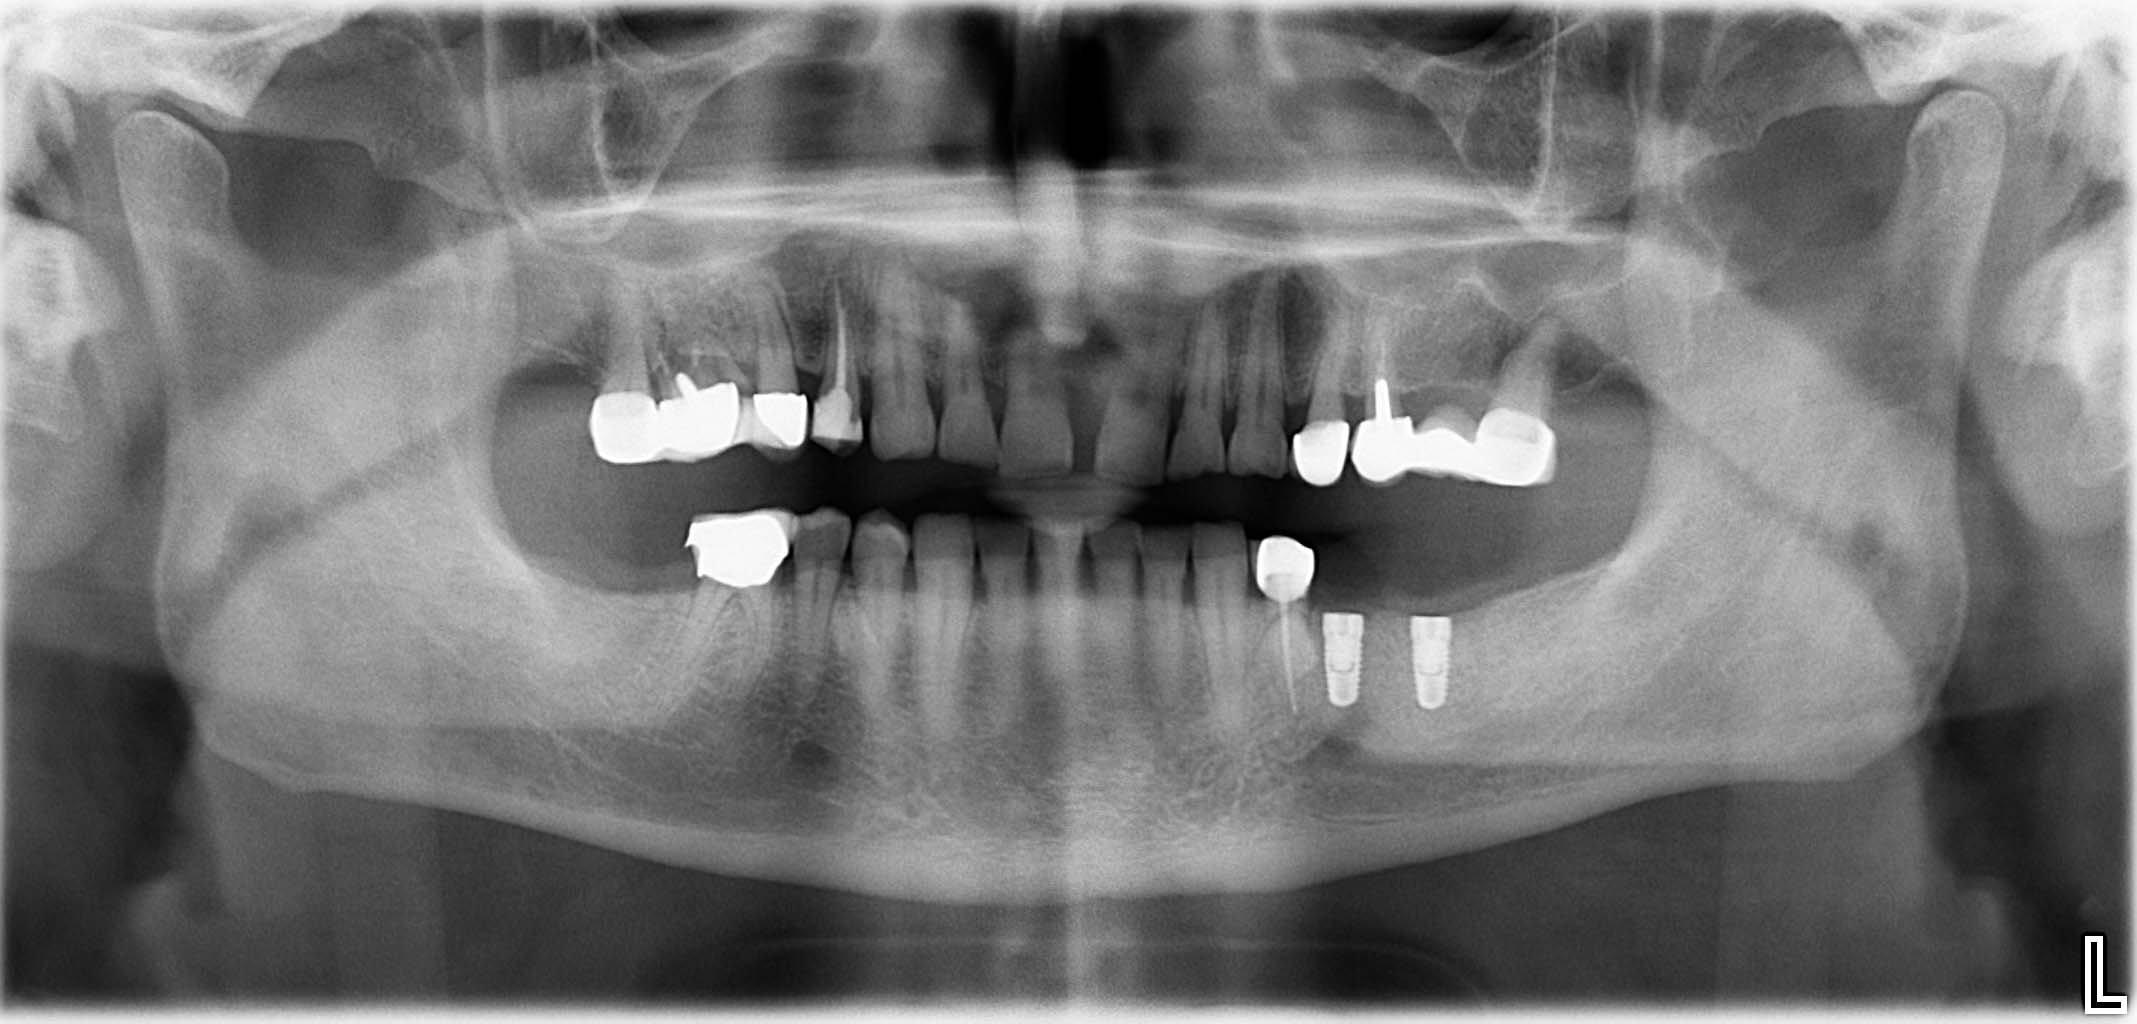

Ausgangssituation: Zahn 36 mit apikaler Beherdung, nicht erhaltungswürdig